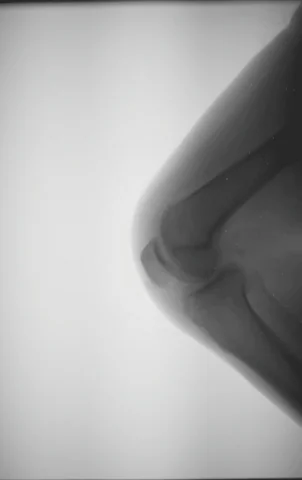

들어는 봤지만, 어딘가 낯선 ‘고관절 탈구.’ 고관절 탈구란 말 그대로 우리 신체 중 엉덩뼈와 다리뼈를 잇는 고관절 부분이 비정상적으로 틀어진 현상을 말해요. 아무래도 감기 같은 증상과 달리 엄마 아빠가 육안으로 식별하기 어려워 조기에 발견하기 힘들어요.💁 오늘은 고관절 탈구 증상에 대해 알아볼게요.

앞서 말했다시피 고관절 탈구는 엉덩이뼈와 다리뼈를 잇는 고관절이 외부로 틀어지며 발생해요.😮 보통 엄마의 배 속에서 거꾸로 있던 아이들이나, 선천적으로 발에 기형이 있을 때, 또는 출생 도중 목이 삐뚤어졌던 아이들에게 발생한다고 해요. 이러한 이유는 보통 선천적인 이유인데요. 이 외에도 과한 신체 놀이, 발달과정 중 부적절한 자세와 같은 환경적인 요인에 의해 발생할 수도 있어요.